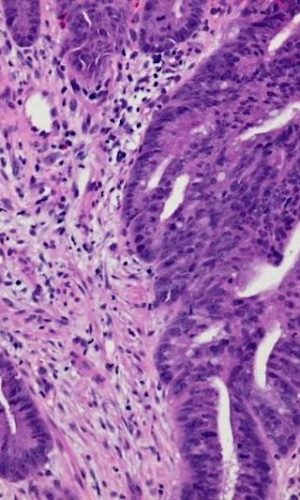

Dr. Shihabi received his anatomic and clinical pathology training at UCSF, completing his surgical pathology fellowship at UCSF with an intense focus on gastrointestinal pathology. Dr. Shihabi is board-certified in Clinical and Anatomic Pathology. At CoCoPath, we offer a breadth of expertise and experience in the diagnosis of various gastrointestinal disorders, including: